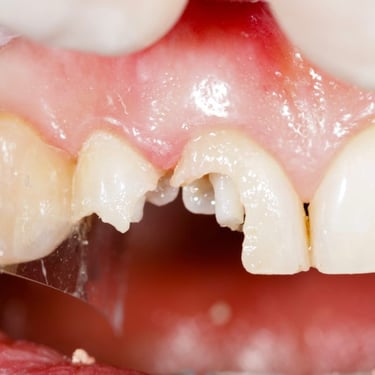

Lesión Traumática Pulpar

Una lesión traumática pulpar es un daño a la pulpa dental debido a un trauma, como un golpe en el diente.

Los pacientes pueden experimentar dolor, sensibilidad y decoloración del diente.

El tratamiento incluye evaluar la vitalidad de la pulpa y, si es necesario, realizar un tratamiento de conducto. Es importante tratar la lesión para evitar complicaciones a largo plazo.

Pulpitis Crónica Hiperplásica

La pulpitis crónica hiperplásica es una inflamación de la pulpa con crecimiento excesivo de tejido pulpar a través de una caries abierta.

Los pacientes notan un tejido rojo que sobresale de la cavidad dental.

El tratamiento incluye la eliminación del tejido afectado y un tratamiento de conducto. Es crucial tratar la caries para evitar infecciones adicionales.